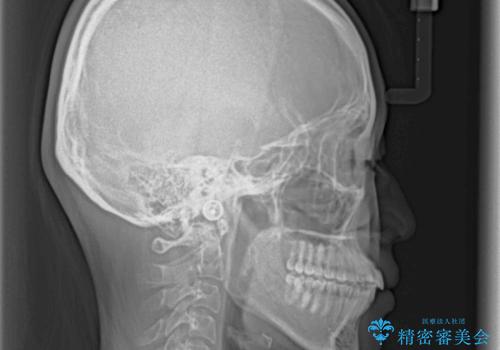

- 飛び出した前歯と全体的なデコボコを気にして来院された患者様です。

ワイヤーでもマウスピースでも治療可能でしたが、自己管理の重要なマウスピース矯正は自分には向かないとのことで、ワイヤー矯正で治療することとしました。

上下歯列全体を後方に移動させるため、親知らずは全て抜歯することにしました。